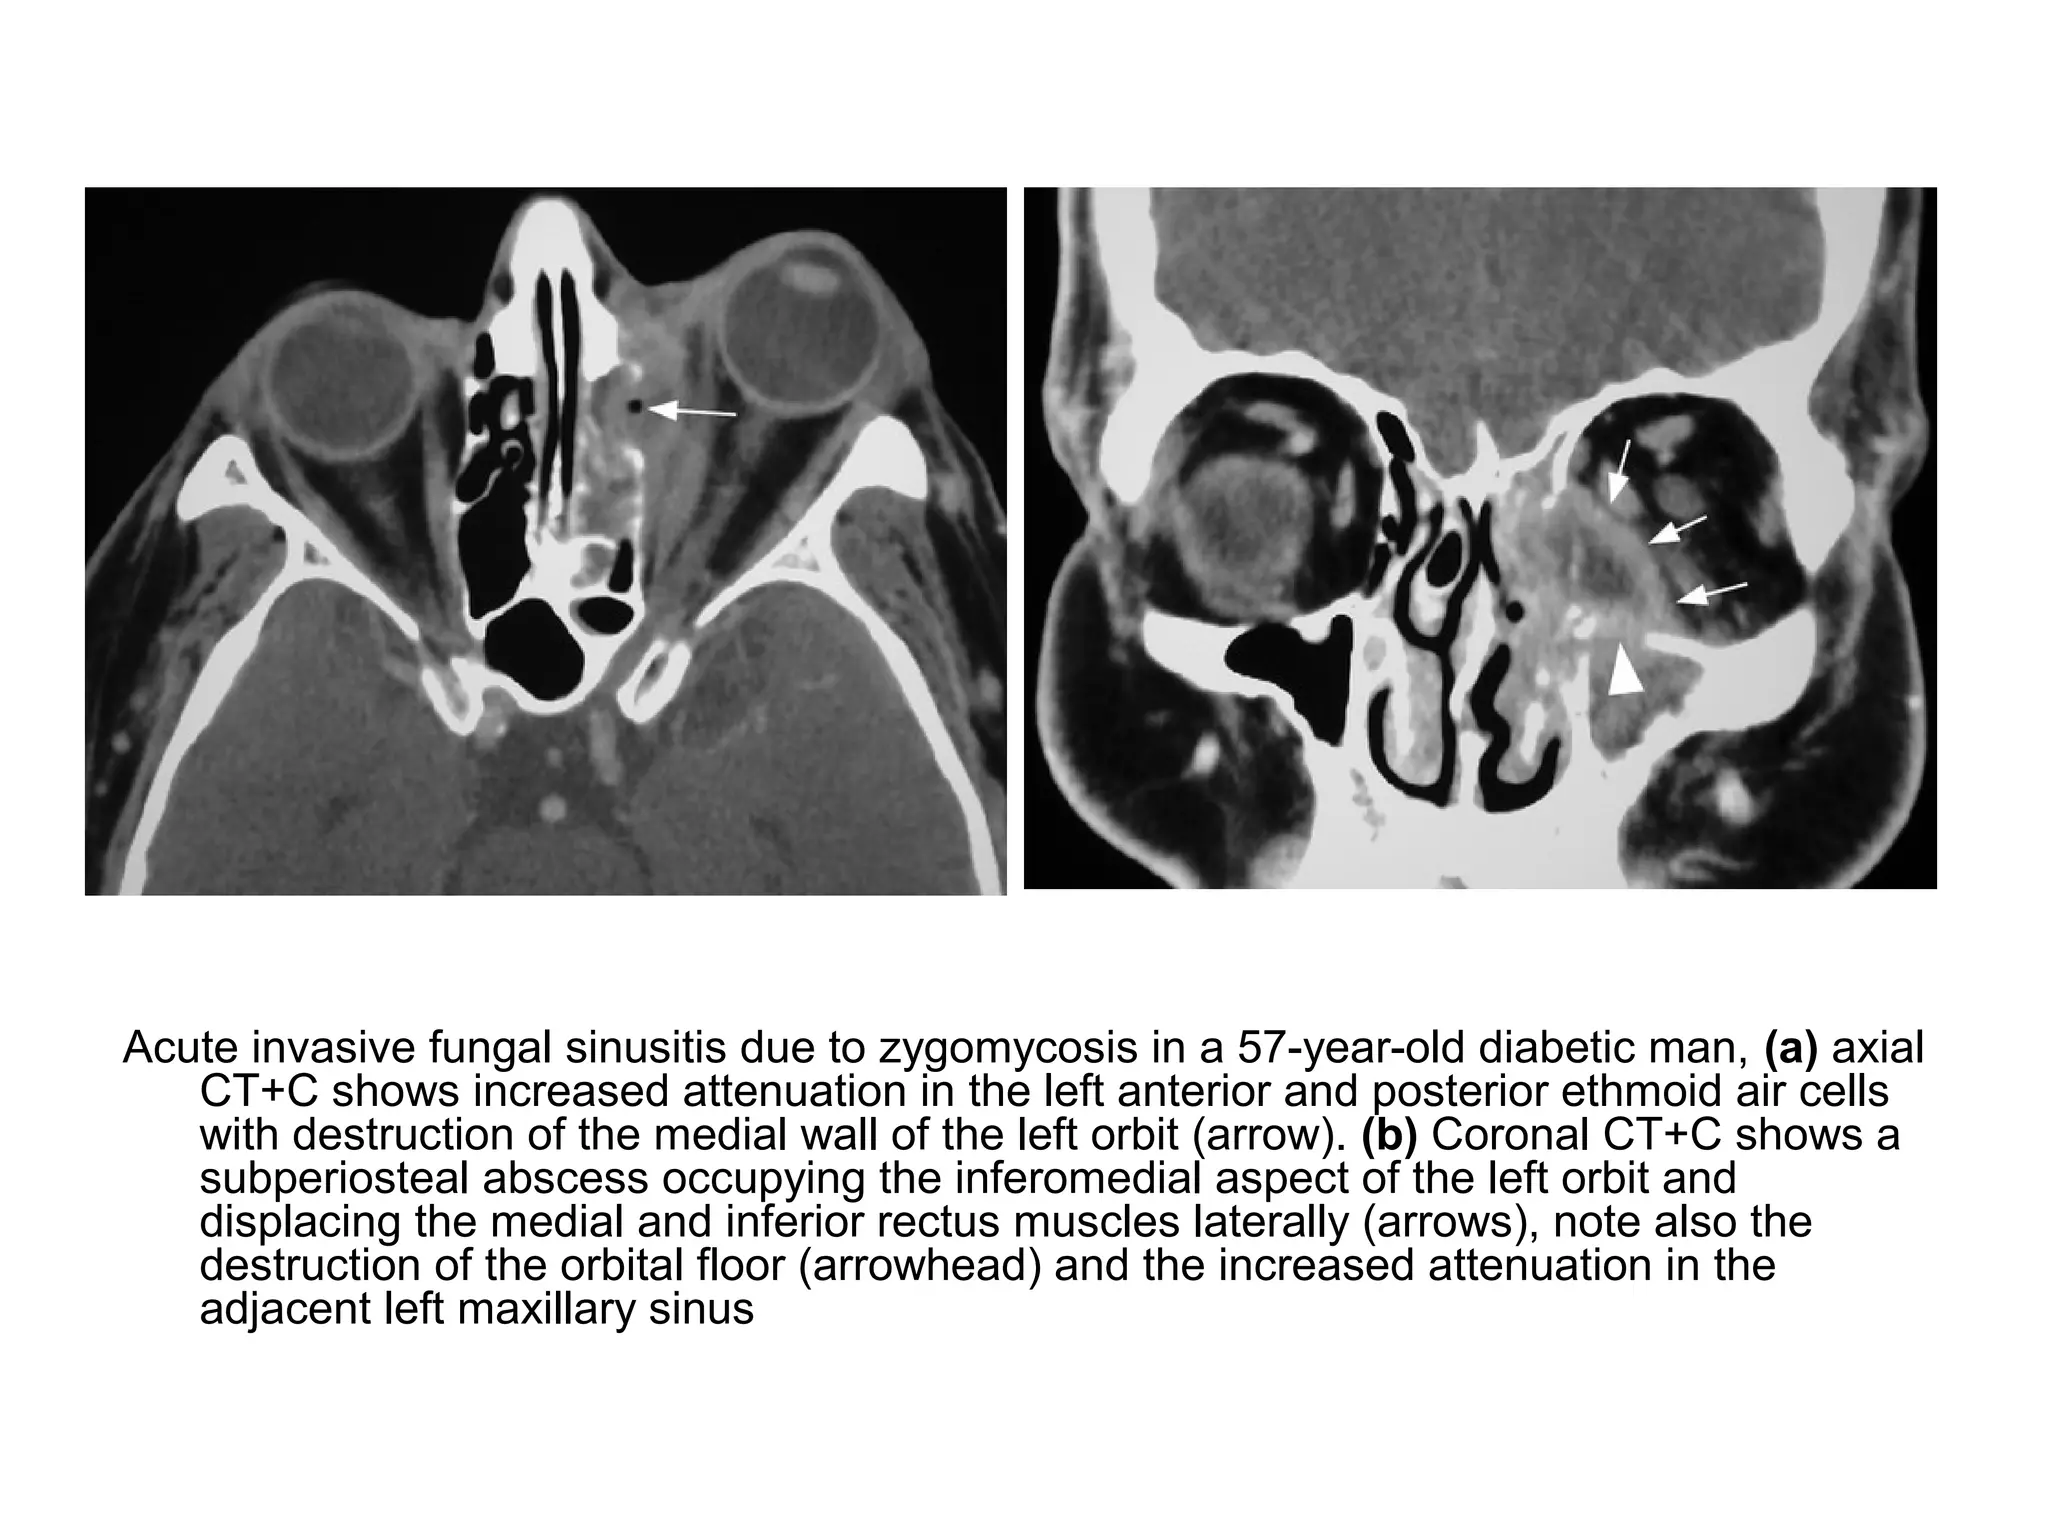

Acute invasive fungal sinusitis due to zygomycosis in a 57-year-old diabetic man, (a) axial

CT+C shows increased attenuation in the left anterior and posterior ethmoid air cells

with destruction of the medial wall of the left orbit (arrow). (b) Coronal CT+C shows a

subperiosteal abscess occupying the inferomedial aspect of the left orbit and

displacing the medial and inferior rectus muscles laterally (arrows), note also the

destruction of the orbital floor (arrowhead) and the increased attenuation in the

adjacent left maxillary sinus